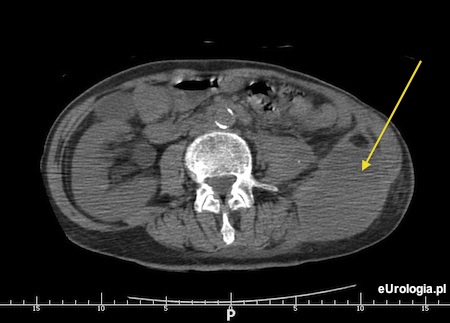

Mój mąż od kilku dni miał gorączkę do 39 stopni i leczony był przez lekarza rodzinnego antybiotykiem. Po kilku dniach leczenia pomimo braku efektu zlecono mężowi wykonanie USG jamy brzusznej. W USG rozpoznano rozległy ropień przestrzeni zaotrzewnowej w miejscu po usuniętej nerce. 5 lat temu mąż miał usuniętą nerkę z powodu roponercza i kamic odlewowej. Przed usunięciem nerki miał na nią kilka operacji kamicy nerkowej. Wczoraj mąż został przyjęty do oddziału urologicznego. Jak postępuje się w przypadku ropnia przestrzeni zaotrzewnowej? Na czym polega leczenie ropnia przestrzeni zaotrzewnowej i czy jest konieczne leczenie operacyjne? Mąż jest bardzo schorowany i boję się, że nie przeżyje kolejnej operacji.